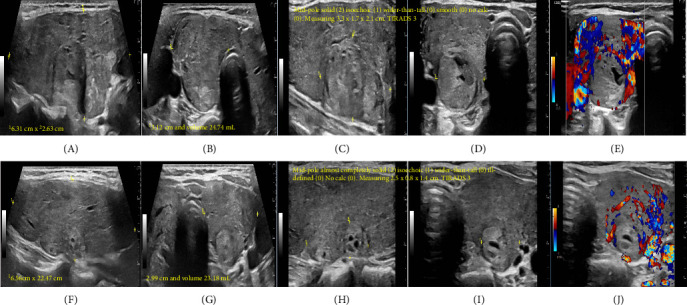

Marine-Lenhart syndrome (MLS) is a rare condition characterized by the coexistence of hyperfunctioning thyroid nodules and Graves' disease (GD). The prevalence of thyroid nodules and thyroid cancer is higher in patients with GD. We report a case of 42-year-old female who presented with thyroid storm and found to have underlying GD. An initial thyroid ultrasound (US) revealed two nodules classified as TIRADS 3, whereas a repeat US after achieving euthyroidism, showed changes in the size and consistency of these nodules and identified a new nodule with classification of TIRADS 6 nodule. A 24-h radioactive iodine thyroid uptake scan demonstrated a diffuse increase uptake (75.1%) with one hyperfunctioning and two warm nodules, including the newly identified TIRADS 6 nodule. Fine-needle aspiration (FNA) biopsy confirmed papillary thyroid cancer (Bethesda VI) in a right (R) warm nodule (the TIRADS 6 nodule), while the other two nodules were benign (Bethesda II). The patient underwent a R hemithyroidectomy that was complicated by recurrent laryngeal nerve (RLN) injury. Pathology examination revealed unifocal papillary thyroid microcarcinoma with positive anterior surgical margin. The patient was furtherly treated with radioactive iodine therapy thyroid nodules with GD should be managed cautiously. Emerging evidence challenges the previous notion that hyperthyroidism provides protection against thyroid cancer. The association between GD and thyroid malignancy remains an area of ongoing investigation, with variable management strategies and prognostic implications reported in the literature.